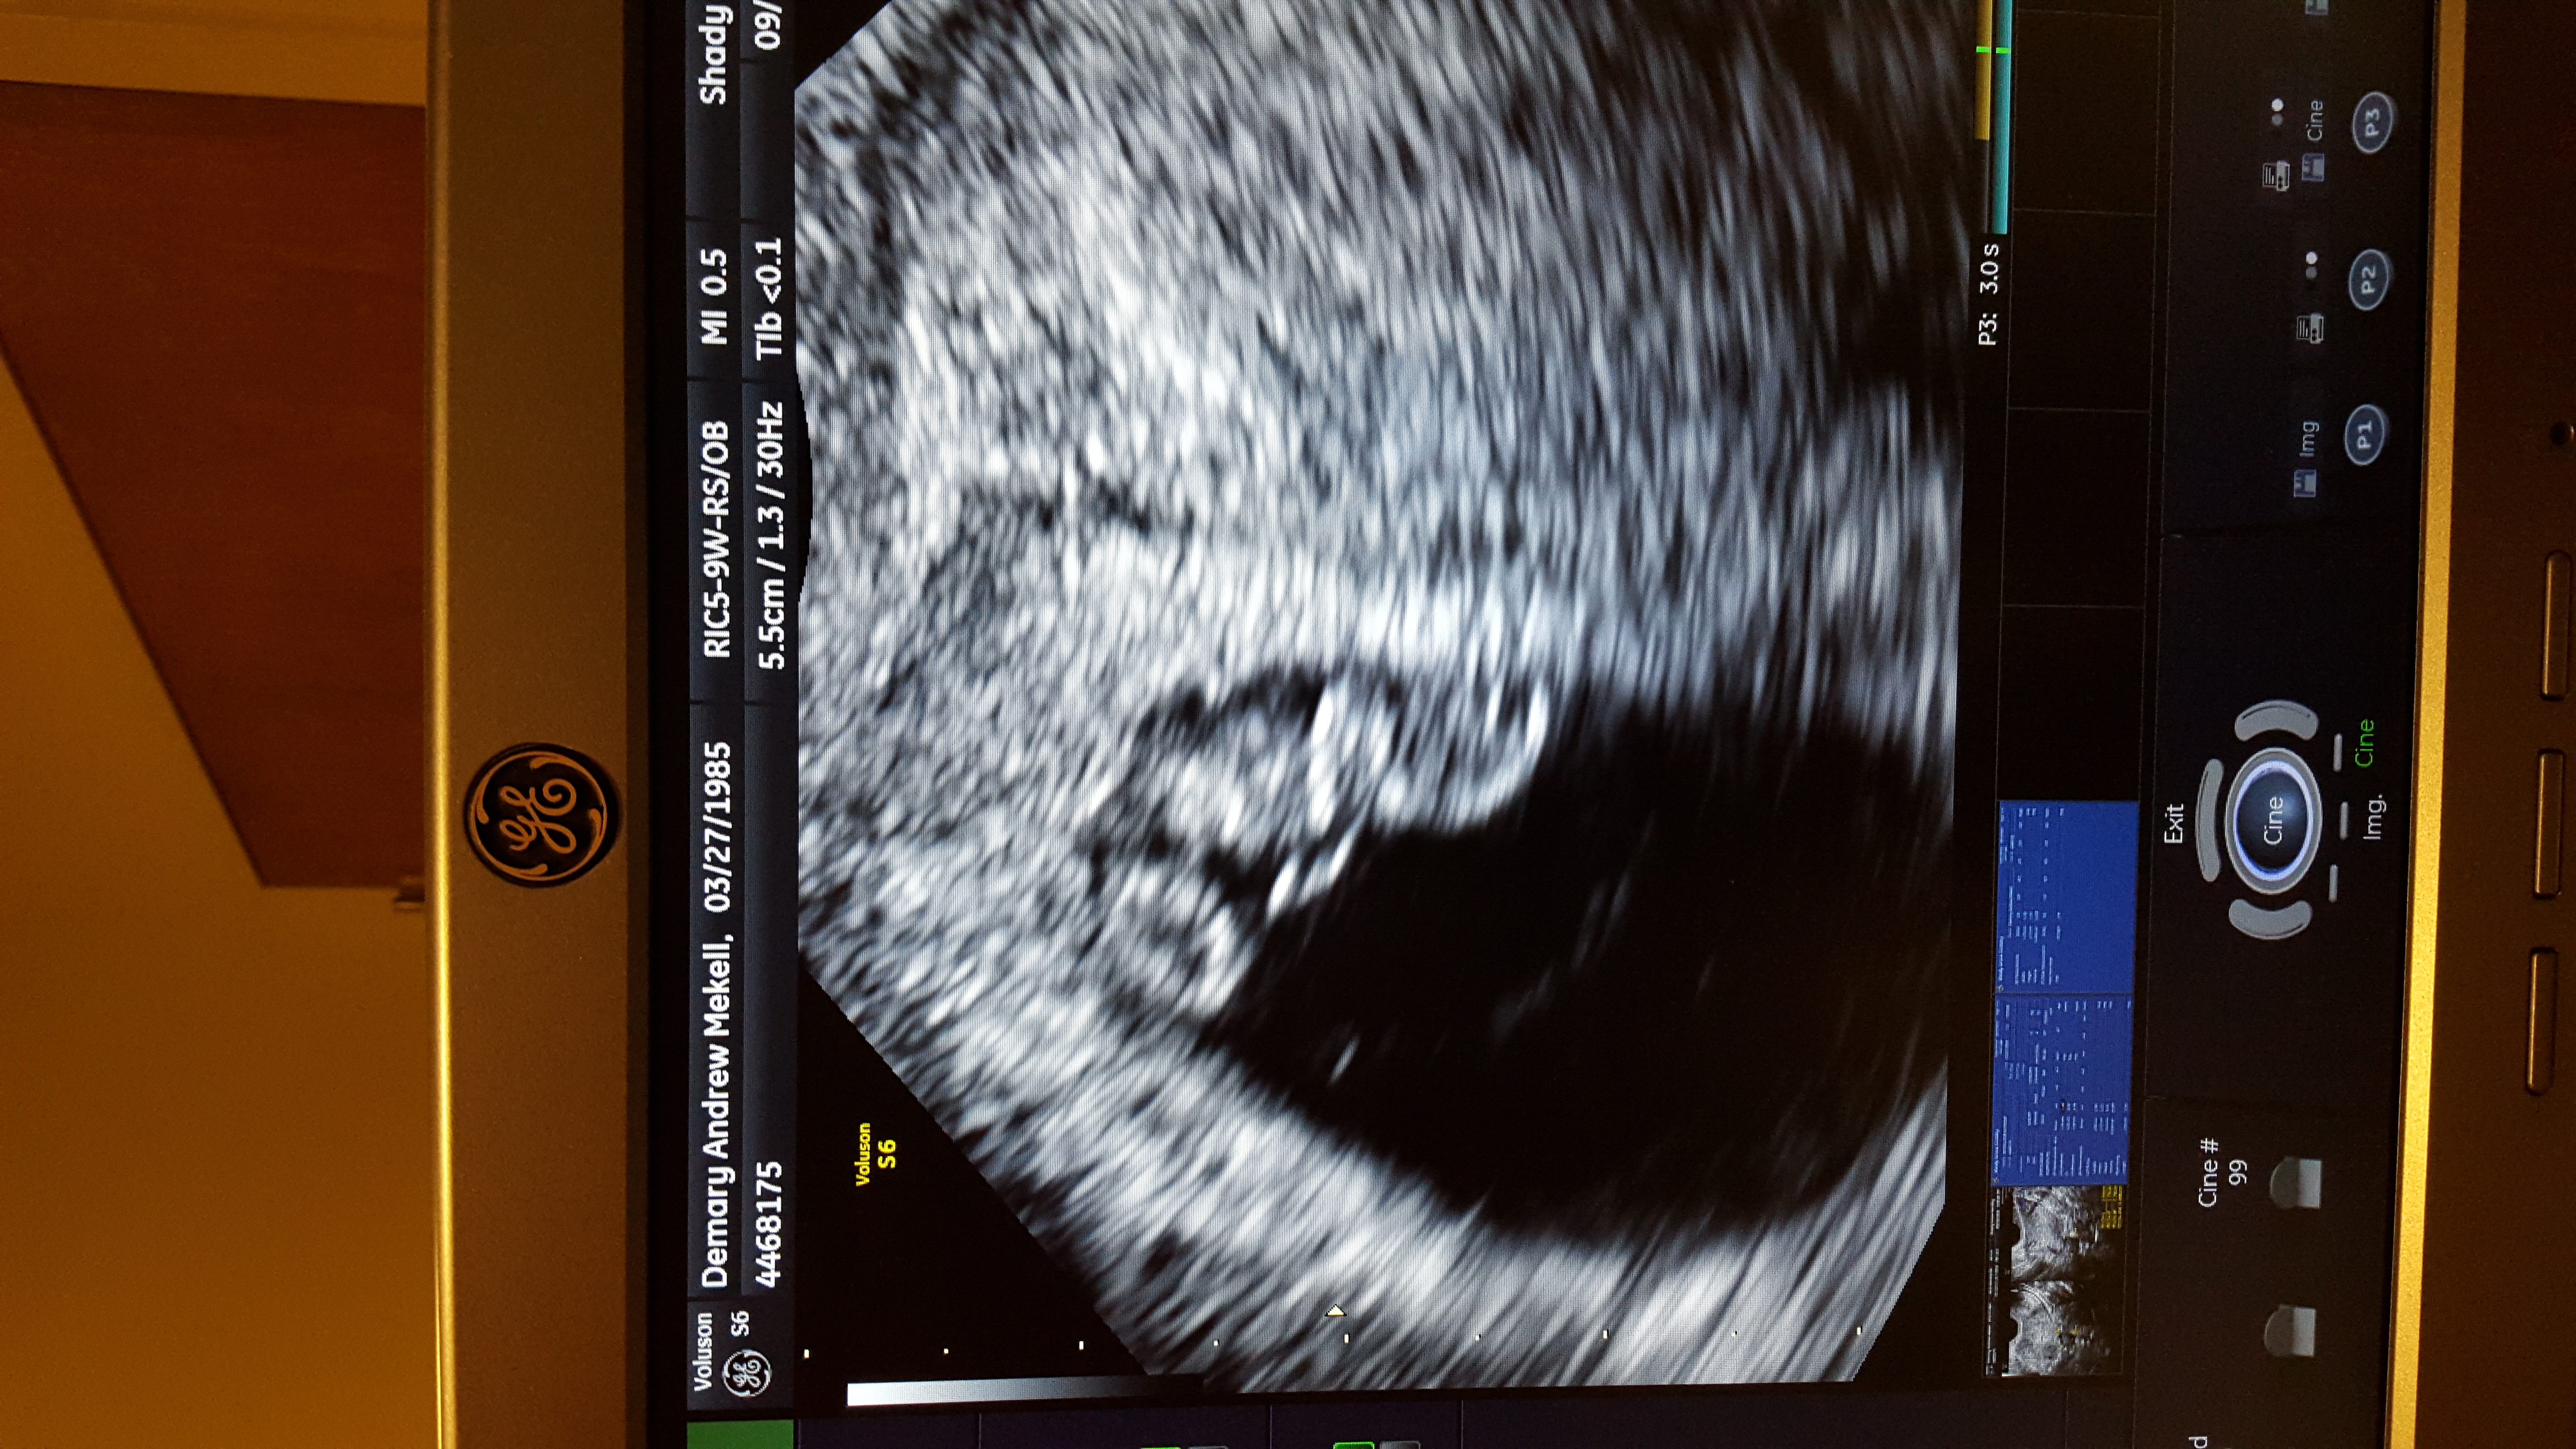

• Another friendly reminder to edit your personal information out of your ultrasounds, mamas!!